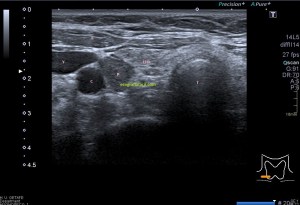

Con la eco pasa igual…cuando queremos estudiar, por ejemplo, el recto anterior del muslo en axial,perfecto…pero en longitudinal, como la imagen 2, se complica porque desde la rótula a la inserción en la cadera, tenemos mucho recorrido. En este caso hacemos lo mismo que cuando hacemos la foto del atardecer…nos ponemos en un extremo, activamos la funciona, recorremos suave y continuamente por la anatomía que queremos fotografiar y ya está…mira la pantalla y no el movimiento de tu mano,como si hicieses la foto, ves la pantalla,pero no como mueves el teléfono.

Es muy útil para lesiones que han crecido mucho y no podemos conjugar en una sola imagen, por ejemplo, un lipoma, cuando superan la medida de la huella de la sonda no son medibles, hay que usar «panoramic view», y como este caso, otros muchos.

Técnicamente es lo mismo, ambos dispositivos hacen una suma de imágenes que se plasman en un resultado final estupendo. Toda la escena más pequeña, pero más alargada que te da percepción de toda la magnitud de aquello que pretendes estudiar, te quita algo de detalle, pero te sirve para medir perfectamente y además puedes incrementar y mover la imagen con tu track ball…

Podemos medir valores superiores a los 15cms con alta calidad de imagen…podemos llegar a medir valores por encima de los 25 cms…es verdad que no todos los equipos tienen este ajuste ecográfico, es decir, es una aplicación y por tanto hay que pagarla.